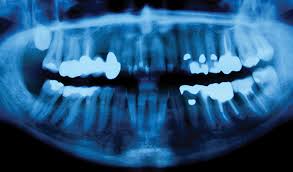

Oral Cancer Overview And More from www.verywellhealth.com Gum cancer is often successfully treated if it is caught early. What bone metastasis looks like. Symptoms are similar to more typical osteosarcomas except that they may occur in very young children and are more widespread. A sore throat or persistent feeling that something is caught in the throat. Abnormal cell growth usually appears as flat patches. Persistent mouth sores that do not heal. This aggressive type of cancer is more likely to spread to the lymph nodes Gum cancers may start out looking like a bump or a sore that does not heal.

Some of the most common oral cancer symptoms and signs include: However, gum cancer symptoms also include white, red or dark patches on the gums, cracking gums, and thick areas on the gums. What bone metastasis looks like. Canker sores can be found anywhere in the mouth from the cheek, inner lip, on and under the tongue, and even in the throat. Sometimes people mistake this for a canker sore (aphthous ulcer).

It may be numb or firm to feel and doesn't fade away over time. Leukoplakia (white and hardened patches) squamous cells is the name given to the flat cells that are present on the surface of the tongue, mouth and lips. Although many jaw growths are benign, they can still do plenty of harm. A white or red patch on the gums, tongue, tonsil, or lining of the mouth. This aggressive type of cancer is more likely to spread to the lymph nodes Oral complications affect the mouth. These cancers usually occur in the thin, flat cells called squamous cells that line the buccal mucosa and other parts of the mouth. Symptoms are similar to more typical osteosarcomas except that they may occur in very young children and are more widespread. Lumps on the roof of your mouth or along your gumline may be the only jaw cancer symptoms you experience. If a tumor spreads to the bone, it's called bone metastasis. Ewing sarcoma also is more likely to be in kids and young. What does a dry socket look like? Osteosarcoma, the most common bone cancer, usually happens to people ages 10 to 30 and most often starts in the arms, legs, or pelvis.